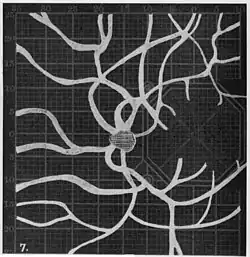

In the 1940s there were further developments. Evans reviewed the state of research in 1942.[6] In 1945, Welt designed a portable campimeter and linked the size of both the blind spot and the angioscotoma to retinal arterial pressure.[7] In the same year, Weekers and Humblet published detailed tracings that overlaid vessel photographs onto Bjerrum screen plots, firmly establishing the one‑to‑one correspondence between vascular anatomy and scotoma shape.[8]

20. Venous engorgement. 21. After pressure over internal 22. Same case, normal. 23. Scotoma after ligation of common carotid. 24. Edematous swelling of nerve and retina. 25, Normal blind spot of other eye. -

Widening of angioscotoma under various conditions (holding head lower than trunk; holding the breath; making digital pressure on the same eye; (a vein) on opposite eye; (an artery) on opposite eye).